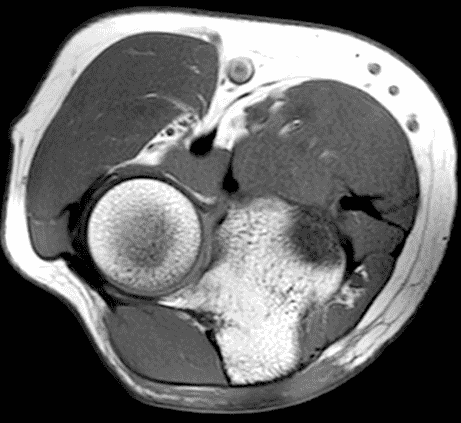

A 55-year-old man complains of pain, numbness, and tingling in the ulnar aspect of the hand and in the small and ring fingers. The symptoms are more severe with elbow flexion and during sleep. He has no muscle weakness or history of trauma. Axial T1-weighted (1A, 1B) and fat-suppressed, fluid-sensitive (1C, 1D) images are shown. What are the findings? What is your diagnosis?

Figure 2: At the level of the cubital tunnel (2A and 2C), identifiable by the thin cubital tunnel retinaculum (yellow arrow), the ulnar nerve (red arrow) is focally enlarged and hyperintense compared to the nerve more distally (2B and 2D), where it lies between the two heads of the flexor carpi ulnaris muscle (asterisks). No soft tissue mass is present.